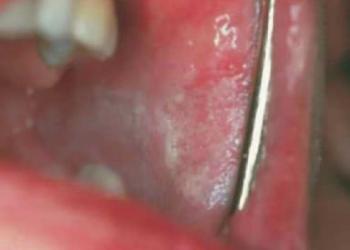

Leukokeratosis nicotina palati

Főleg pipások keményszájpadjának fehér hiperkeratotikus elváltozása, a kis nyálmirigyek gyulladt kivezetőcsöveit mutató pici piros foltokkal (10.15. ábra)

10.15. ábra. Leukokeratosis nicotina palati

(Gera I. felvétele)